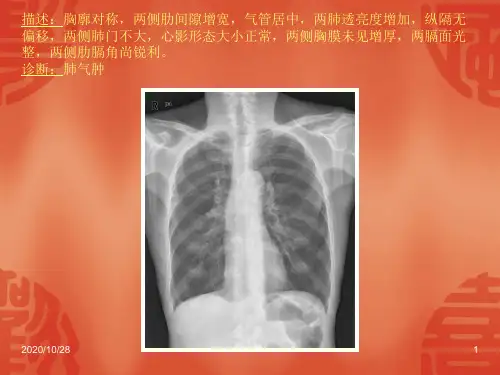

X线表现:

早期可无异常 间接征象:a.阻塞性肺气肿 b.阻塞性肺炎 c.阻塞性肺不张 直接征象:肺门肿块,或伴 有肺门淋巴结增大。